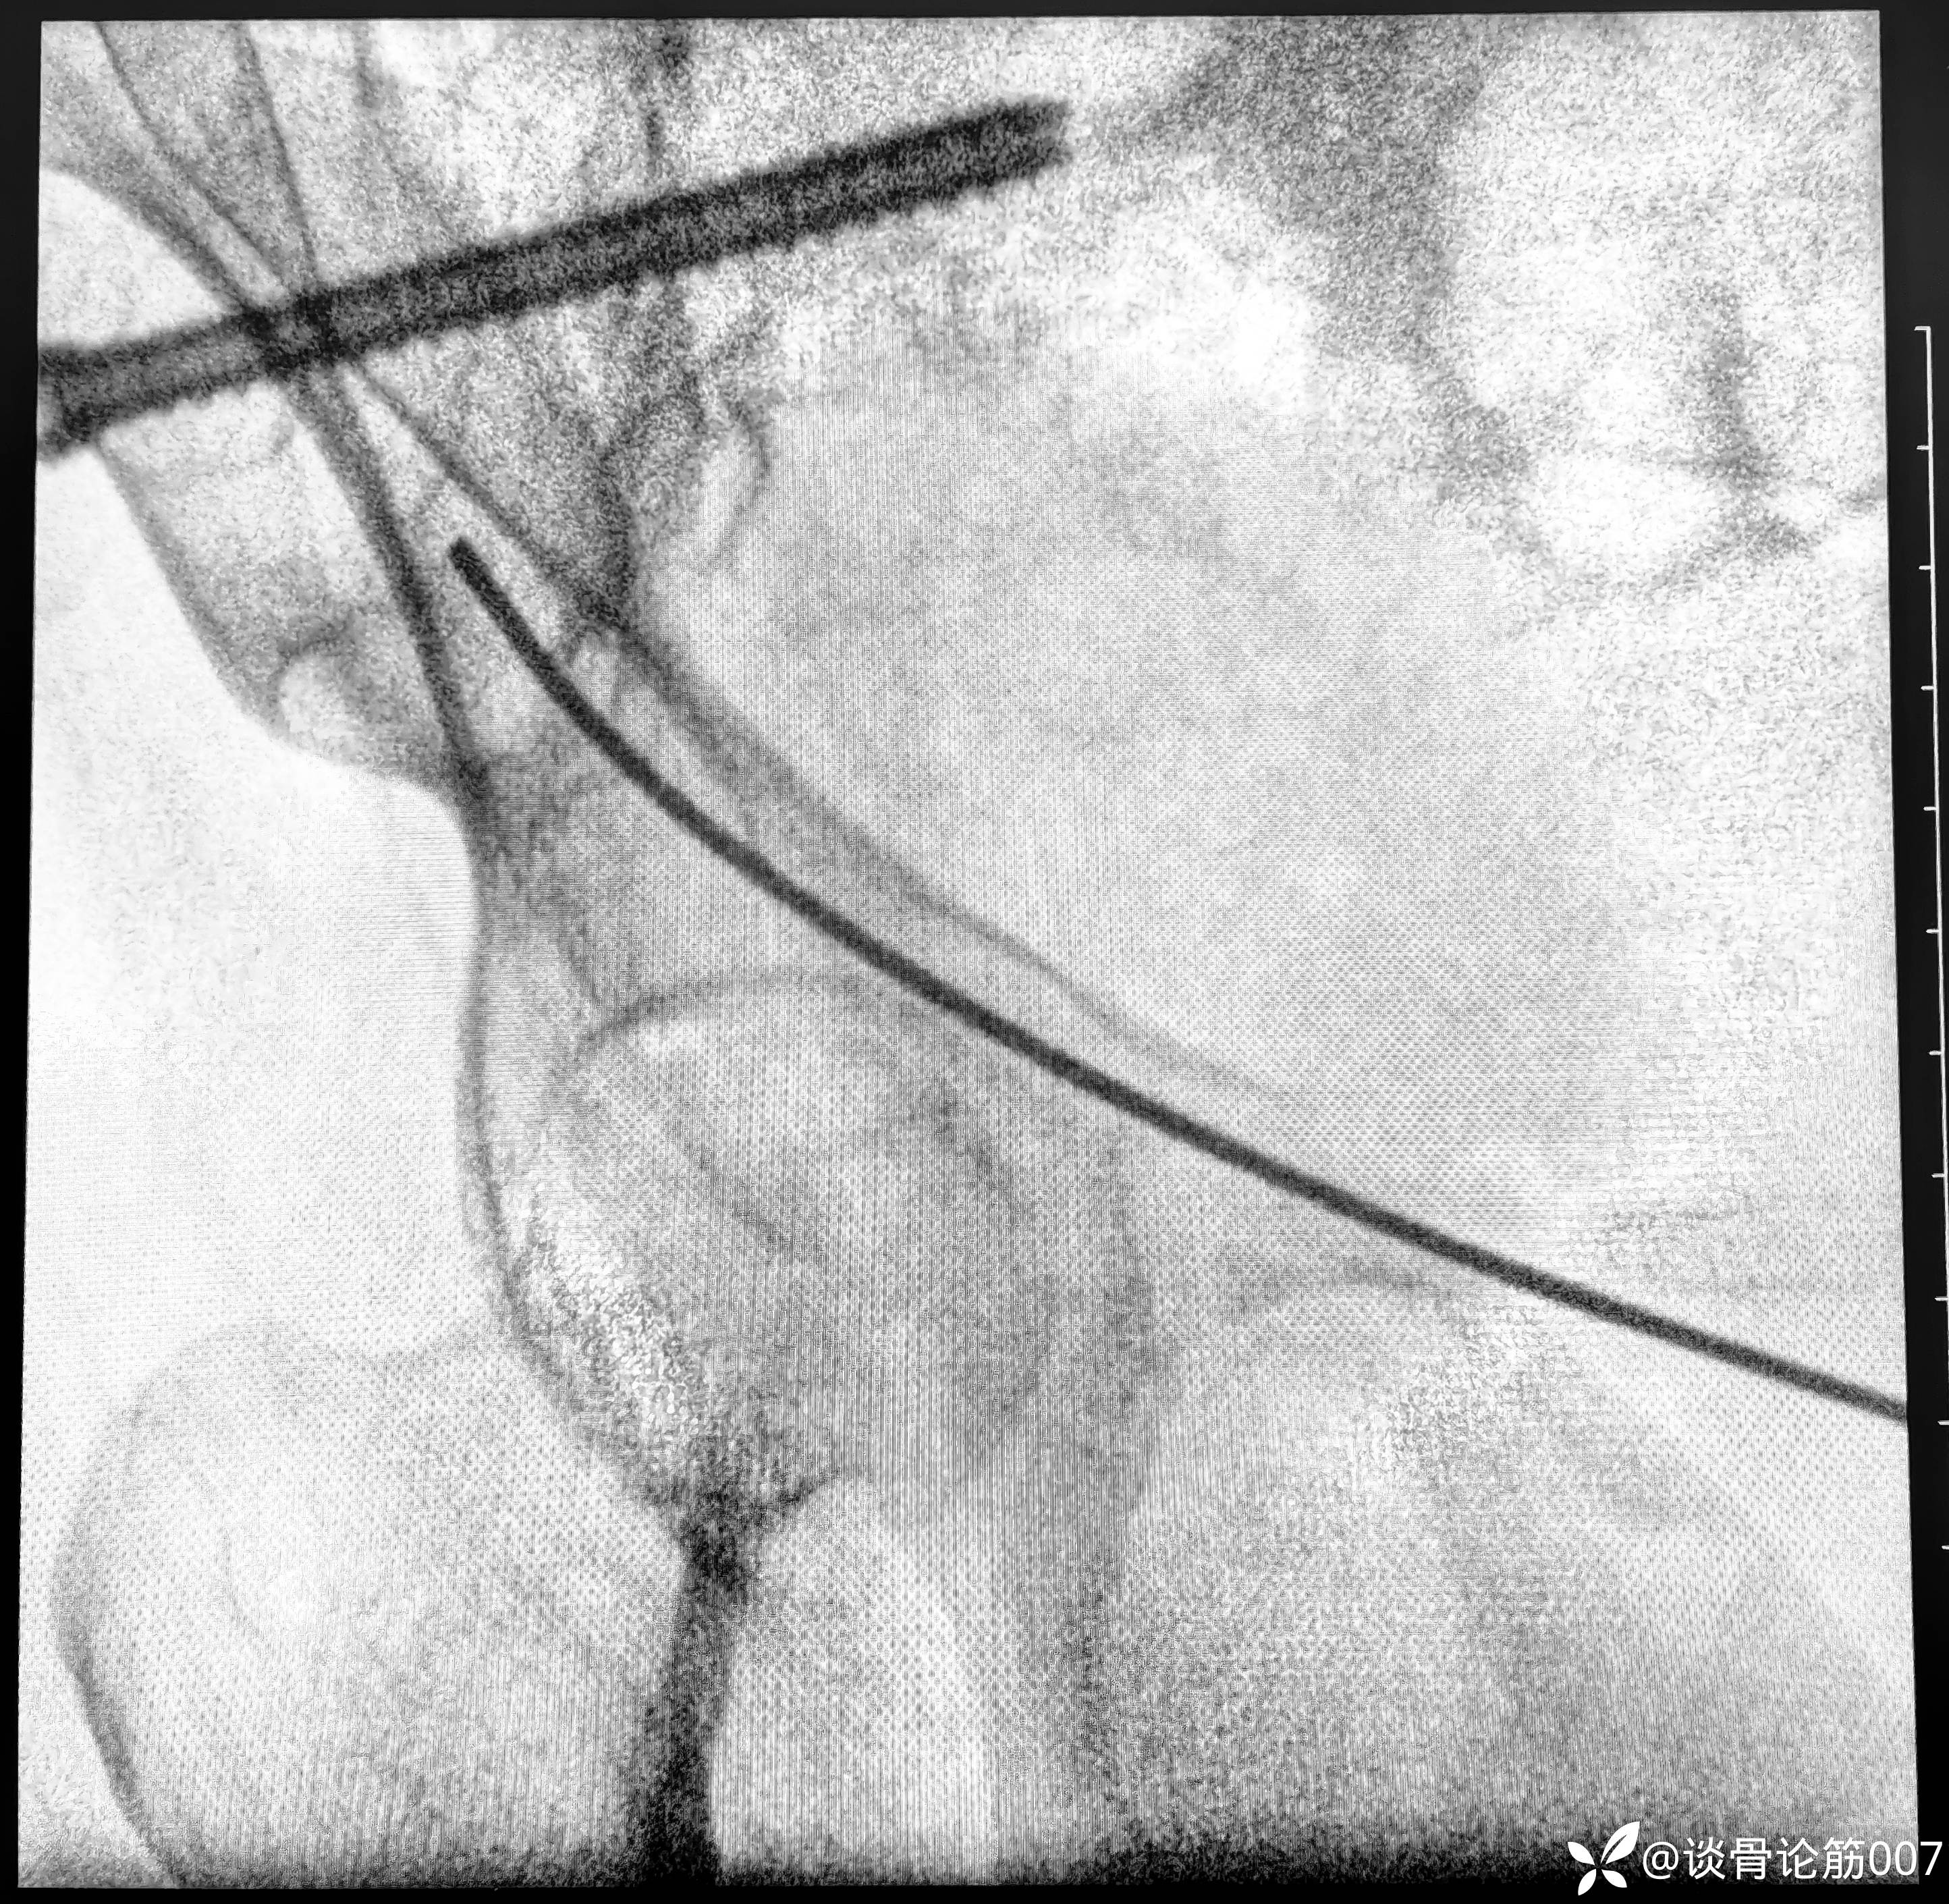

钉道方向还是有点差强人意

耻骨上支螺钉通道有限,如果有5.0空心螺钉更方便,但5.0螺钉没有长的,3.5长螺钉对耻骨上支骨折复位作用差一点,因为是实心,对操作要求更高一点。